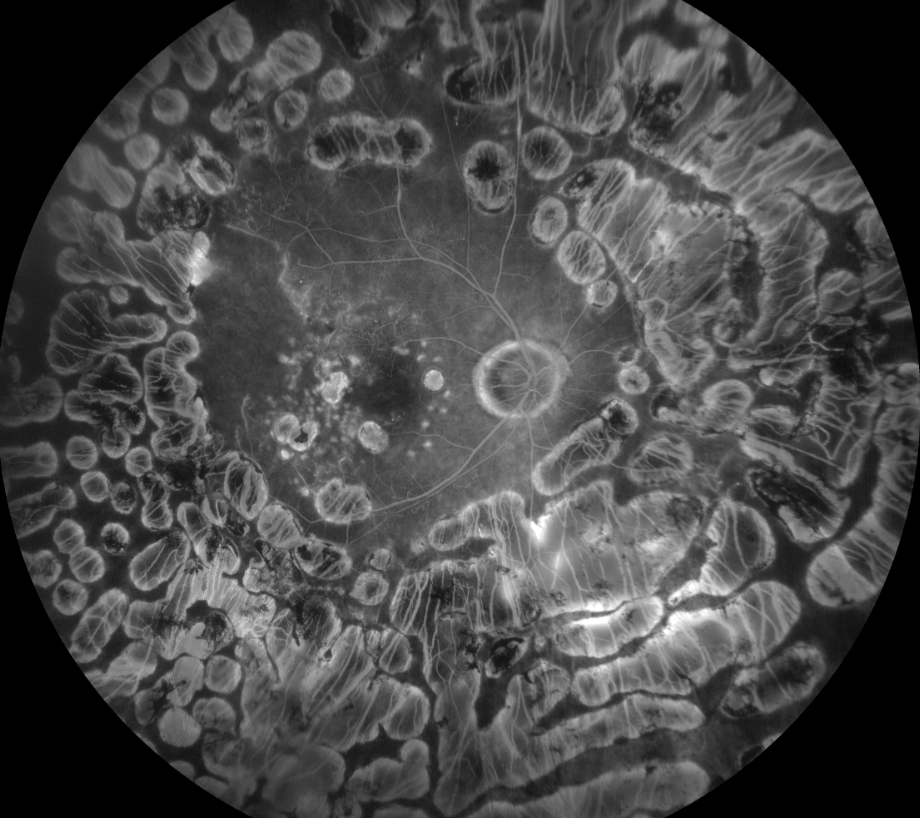

后葡萄膜炎可能带来难以解决的视力和眼部健康问题,且有效的治疗选择很少。2011年的多中心葡萄膜炎类固醇治疗试验(MUST)恰恰展示了制定可接受治疗方案的难度。这项前瞻性随机对照试验在三大洲的23个三级医疗中心开展,探索了眼部与全身免疫抑制的疗效。

数据显示,玻璃体内氟轻松丙酮化物眼部免疫抑制与全身免疫抑制在控制眼内炎症方面效果相当,在视力、黄斑囊样水肿和葡萄膜炎控制方面的结果在统计学上相似。不幸的是,其不良反应较为严重,最终在大多数情况下成为了阻碍因素。

迈阿密 Bascom Palmer 眼科研究所的 Rami Aboumourad 医生指出:“玻璃体内氟轻松丙酮化物治疗具有更高的眼部发病率,白内障形成率增加,眼压变化超过10mmHg,且需要药物或手术干预的青光眼性损害发生率升高。” 他还提到:“理论上,在使用氟轻松丙酮化物植入剂之前,可先使用短期类固醇(如玻璃体内曲安奈德)来减轻类固醇反应,但这并非万无一失,也无法解决白内障风险问题。”

Rami Aboumourad 医生表示,尽管氟轻松丙酮化物植入剂能快速控制炎症,但仅在单侧使用时具有成本效益,且会带来显著的眼部副作用,包括24个月内白内障高风险。

他还称:“玻璃体内氟轻松丙酮化物治疗在生活质量评分上仅略高于全身治疗,且全身不良事件发生率相似。最终,该研究未能证明玻璃体内氟轻松丙酮化物优于全身治疗。”

为什么要关注 MUST 试验?Rami Aboumourad 医生强调,接受玻璃体内氟轻松丙酮化物治疗的患者需要持续监测眼压,特别是使用植入剂而非玻璃体内药物递送的患者。这项研究展示了玻璃体内皮质类固醇在管理眼内炎症方面的有效性,同时也揭示了相关风险和局限性。

目前有一项IV期试验正在评估低剂量氟轻松丙酮化物植入剂(0.18mg,而非0.59mg)。Rami Aboumourad 医生指出:“我们期待看到调整剂量后能否在有效控制炎症的同时改善副作用情况。” 其他试验正在探索玻璃体内递送的类固醇节约药物。